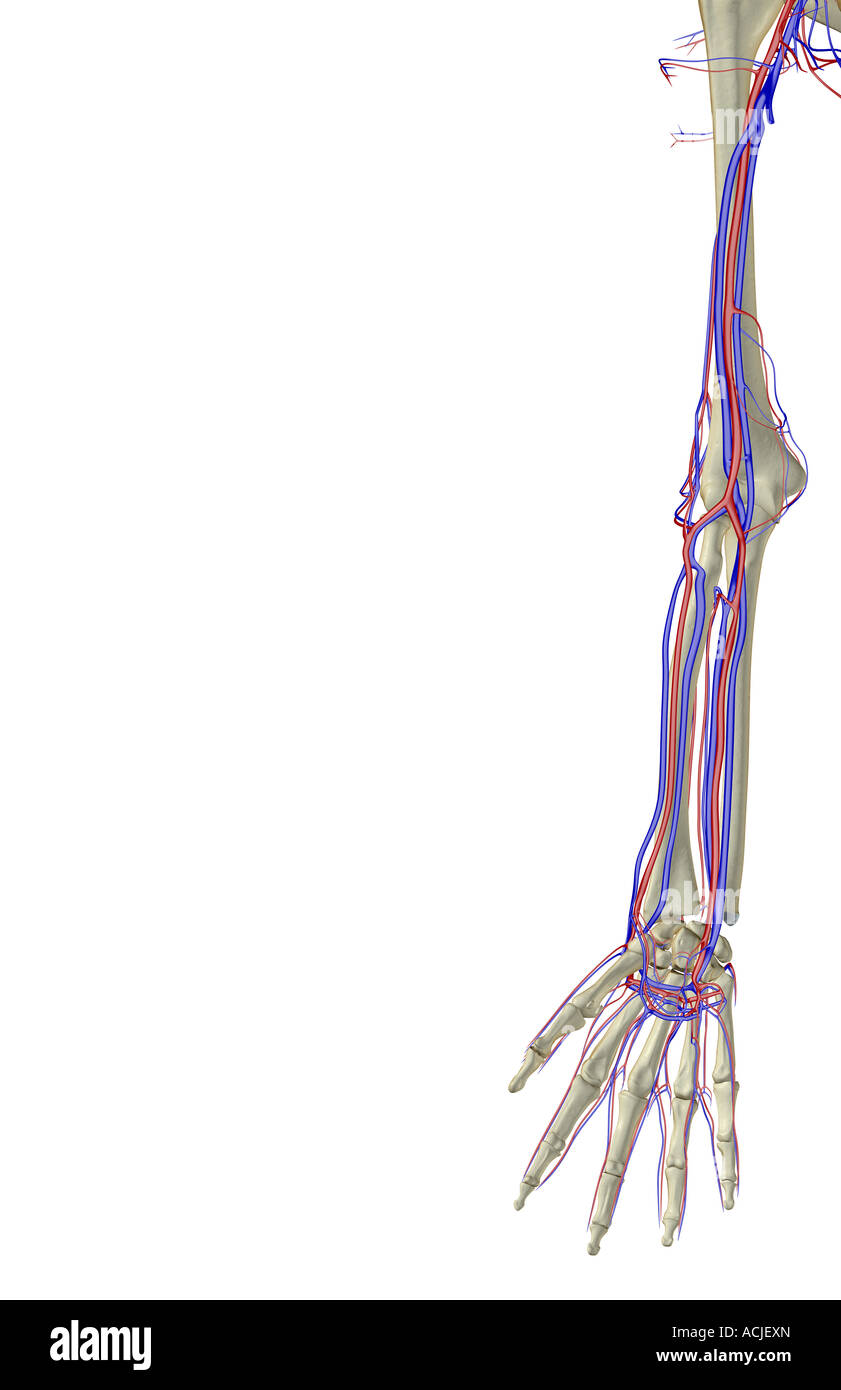

The blood supply of the upper limb Stock Photohttps://www.alamy.com/image-license-details/?v=1https://www.alamy.com/stock-photo-the-blood-supply-of-the-upper-limb-13169948.html

The blood supply of the upper limb Stock Photohttps://www.alamy.com/image-license-details/?v=1https://www.alamy.com/stock-photo-the-blood-supply-of-the-upper-limb-13169948.htmlRFACJEXN–The blood supply of the upper limb